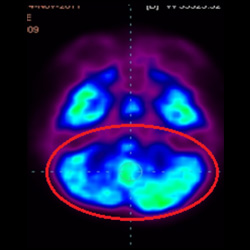

細胞治療后,藍色和黑色區域減少,并且看到更活躍的區域。這表明損傷減少并改善了大腦功能。

細胞治療前 PET CT 掃描顯示神經組織中的藍/黑色區域,表明腦癱引起的大腦損傷。

這證明細胞療法是治療腦癱兒童安全有效的方法。細胞療法可以更新大腦損傷的核心,并且可以通過 PET CT 掃描來監測大腦的改善情況。這些細胞療法與標準治療一起促進腦癱兒童的生長和改善。